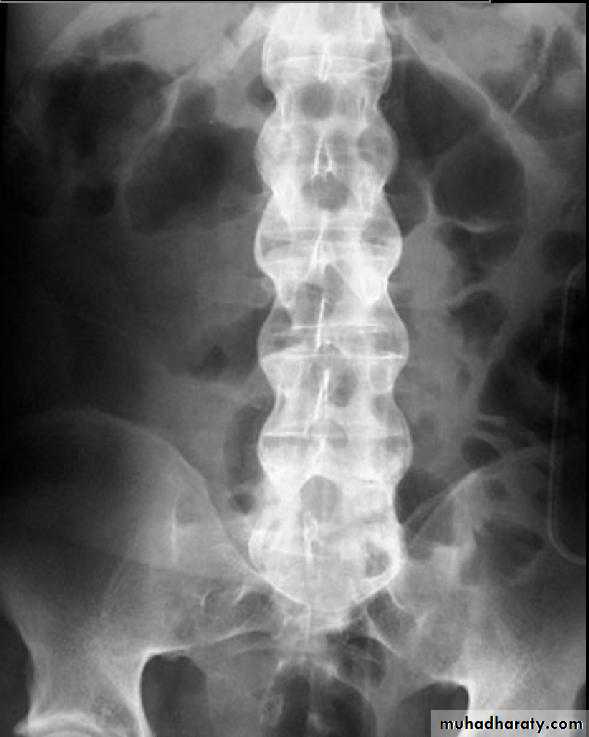

In the Spine :

* Lower cervical and low lumbar spine are most comonly affected.* Osteophytes may encroach on neural foramina (best seen on oblique views).

*Vacuum phenomenon: gas (N2),is pathognomonic of the degenerative process.

* OA of the spine occurs in the apophyseal joints .

* Degenerative spondylolisthesis (pseudospondylolithesis)

Lumbar spondylosis. There is distal narrowing and a vacuum

phenomenon is present in the degenerative discs. Marginal osteophytes arepresent. Inferiorly the facet joints show features of degeneration and, with the increase in lordosis, the spinous processes are in contact